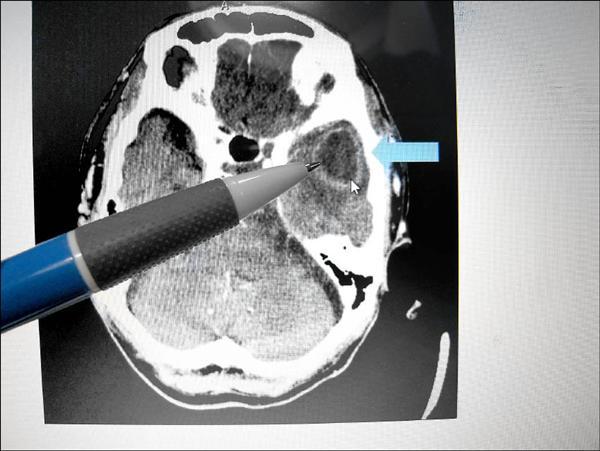

澄清院中港院神科崇文昨天表示,名男子是位夫,他曾因痛到其他院住院1,出院後他得病依,又到澄清院神科就,就天突然作、全身抽搐,由於他之前有病史,疑是部疾病致痛,而造成全身抽搐,急接受和核磁共振等查。

果他的左部有一3.5公分大的,因的不小,由神外科其手,清除菌感染部位,再接受抗生素治,他才痊。